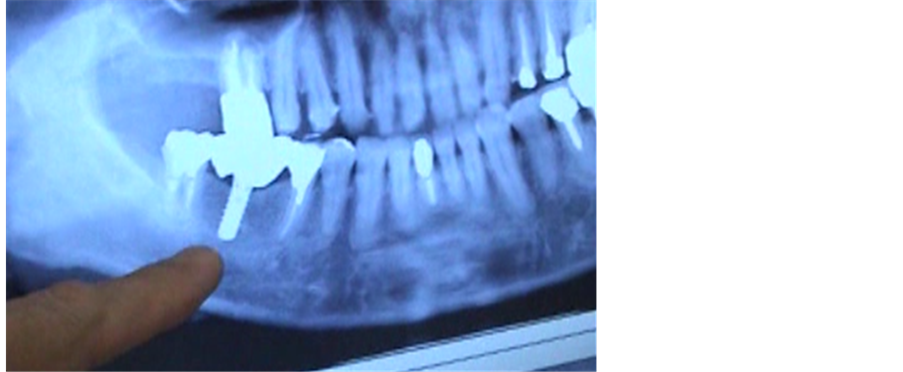

A 48-year-old woman was suffering from dizziness, unsteadiness, and a sense of fatigue for several years. A titanium dental implant had been placed in her lower alveolar bone (Figure 1). To determine if the patient’s symptoms were being caused by her implant’s collection of electromagnetic waves, several tests were performed. First, the patient was placed immediately in front of a PC screen. At such a close distance, she could not maintain her balance (Figure 2). When the PC screen was covered with aluminum foil to block the electromagnetic

Figure 1. The titanium implant in the subject’s right lower alveolar bone.